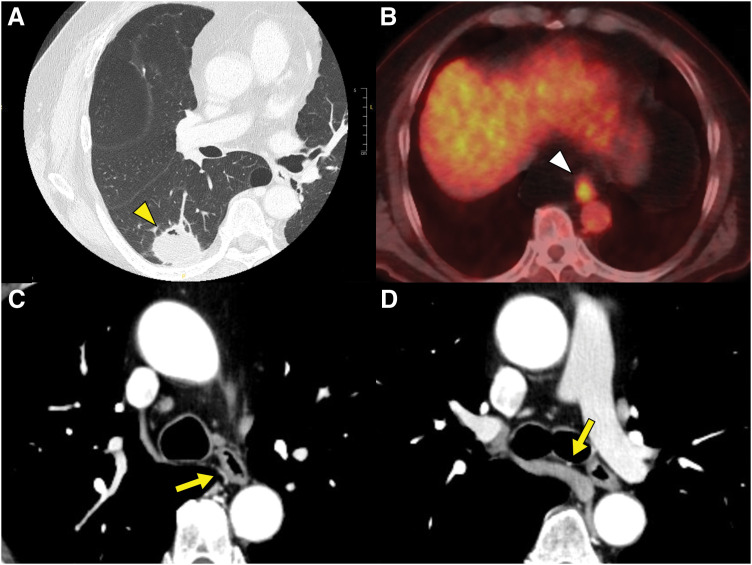

Case presentation: A 64-year-old male with a history of heavy smoking was referred to our hospital after an abnormal mass was detected on a chest radiograph during an annual health check. Chest CT revealed a 3.7 cm consolidative mass in the right lower lobe, resulting in a diagnosis of primary lung cancer, classified as T2aN0M0, stage IB. Additionally, abnormal fluorodeoxyglucose (FDG) uptake was observed in the lower thoracic esophagus, leading to a diagnosis of synchronous esophageal cancer, classified as T1bN0M0, stage I. As both lesions required upfront surgical resection via the right thoracic cavity, a single-stage esophagectomy and right lower lobectomy were planned. Initially, esophagectomy was performed using a five-port video-assisted thoracic surgery (VATS) approach in the prone position from the right side. To preserve the blood supply to the fifth intercostal muscle for subsequent harvesting as a muscle flap, the utility port in the corresponding intercostal space was placed as ventrally as possible. The esophagectomy was performed while preserving the right main bronchial artery. The patient was then repositioned to the left lateral decubitus position, and the preserved fifth intercostal muscle flap was harvested. A right lower lobectomy was completed, preserving the bronchial artery, and the bronchial stump was reinforced using the harvested muscle flap. Despite postoperative development of esophagogastric anastomotic leakage, the patient did not develop a BPF, and no signs of BPF have been observed during 12 months of follow-up.